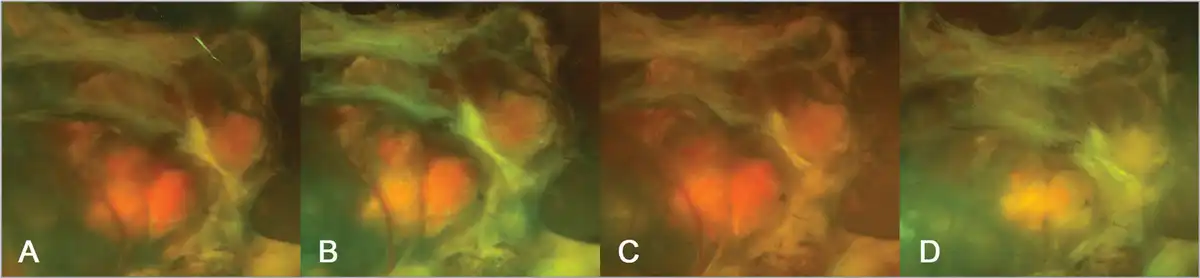

A 24-year-old woman was diagnosed with von Hippel-Lindau (VHL) syndrome, which manifested as cerebral, spinal, and retinal hemangioblastomas (RHB). Although she underwent multiple surgeries to save her vision, her right eye's condition worsened to no light perception (NLP). As a result, it was decided to observe her without additional ophthalmic treatments. Treatment was started on belzutifan (Welireg, Merck) on October 12, 2023, due to neurologic indications. Remarkably, within just 2 months, there was a significant reduction in the size of the RHB in her right eye. Figure 1A–C displays fundus photographs of the patient's eye, taken 12, 8, and 4 months before starting treatment with belzutifan, showing the stable condition of the RHB. Figure 1D shows the fundus photograph of the same eye, captured just 2 months following the initiation of therapy. A dramatic response to the treatment is evident, characterized by fibrosis and shrinkage of the RHB.

Advanced proliferative vitreoretinopathy with large central retinal hemangioblastoma in detached retina demonstrating progressive activity of the lesion (A) 12 months, (B) 8 months, and (C) 4 months prior to belzutifan. (D) Two months following initiation of belzutifan, the lesion has demonstrated complete regression.